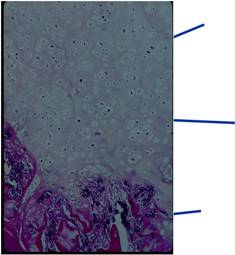

Pathology:

- Medullary and cortical continuity w/ underlying bone

- Hyaline Cartilage Cap with lobular growth

- Cartilage cap involutes after growth

Gross Pathology

- The osteochondroma is completely covered in periosteum

- Cut surface shows hyaline composition of cartilage cap

Cap

- Younger patients thicker cap because of growth hormone

- Smooth or knobby

- 2 mm to 1 cm thick

Beneath the cap, calcified cartilage which appear as white deposits are present

Microscopic Pathology